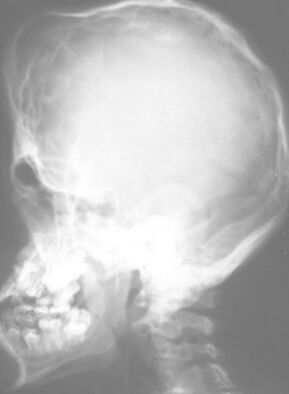

8.圖示X光片,顯示何種手術併發症? (A)拔牙傷口流血不止 (B)魯特維氏咽峽炎(Ludwig's angina) (C)局部麻醉藥注射針頭斷裂殘留 (D)下顎骨骨折